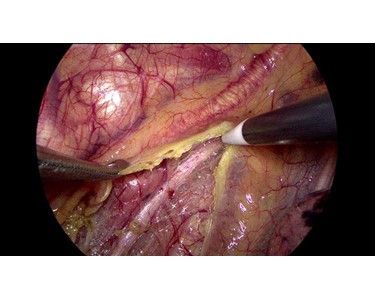

Accurately restore organs and tissues in their real colour for perfect identification of blood vessels, lymph nodes, and nerves.